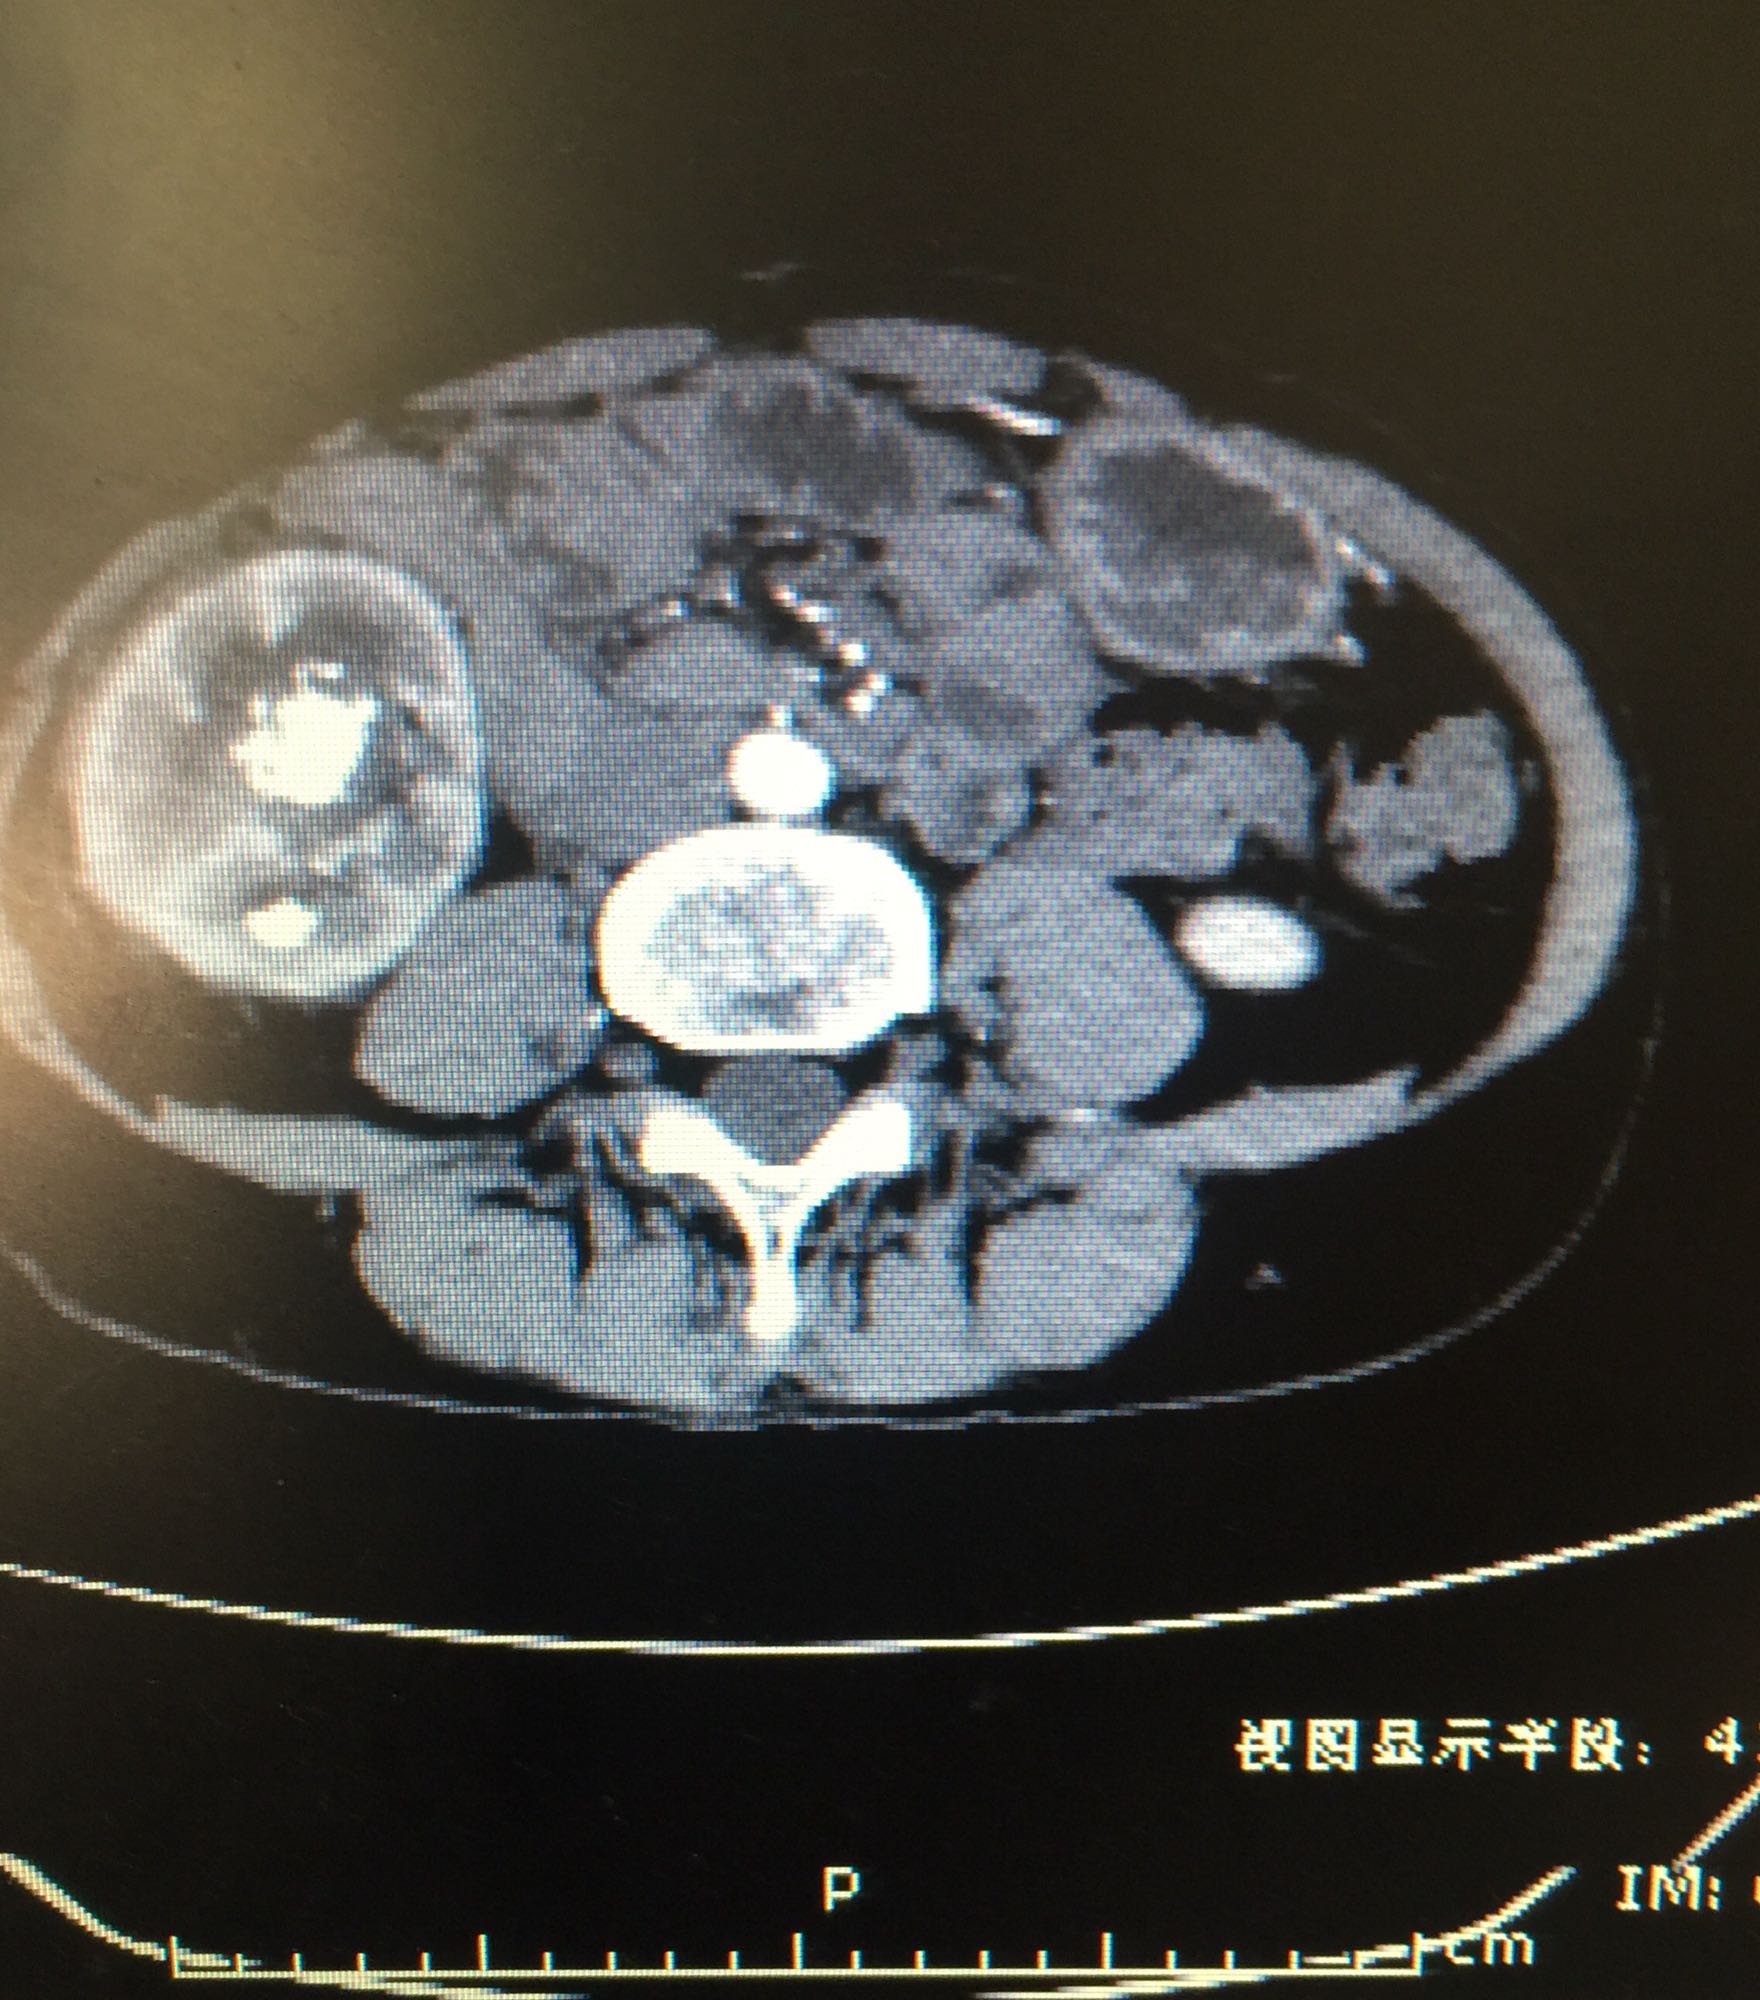

右侧肾脏巨大铸型结石一例

肾盂积水伴输尿管肾盂连接处梗阻 肾结石

右侧肾脏巨大铸型结石,右肾盂输尿管连接部狭窄? 拟完善GFR测定后决定下一步治疗方案,目前倾向于开放手术。

该患者结石大,且负荷大部分位于肾盂,肾盂几乎被填满,所以考虑是否有右侧输尿管肾盂连接部狭窄可能,结石负荷大,结合上述情况可行开放手术,一期整形 。 但若为UPJO,患者肾脏积水轻,肾脏皮质厚,肾功影响小,可能性相对小。行PCN结合超声吸附,一期清理肾盂内结石应该问题不大。 对于该患者的治疗,不知大家意见如何?